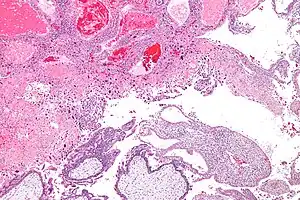

Micrograph of intermediate trophoblast and a hydatidiform mole (bottom of image). H&E stain.